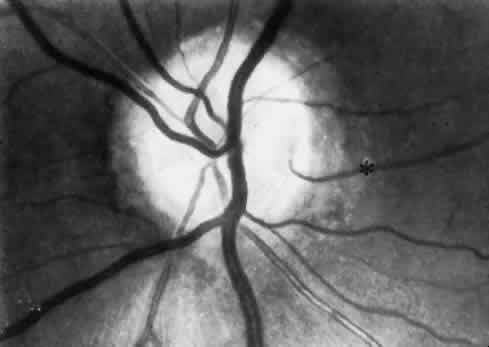

body and iris. Each regional microcirculation is discussed individually. RETINA An understanding of the retinal vasculature and microcirculation is crucial for diagnosis and treatment of acquired retinal disease states, because the vast majority of nonheritable primary retinal diseases are vascular in origin. The retinal blood vessels exist to provide nourishment for the inner retinal layers and to carry off waste products from them. The outer retinal layers are normally avascular and are supplied through diffusion from the choriocapillaris. Despite this dual circulation to the retina, there appears to be functionally little overlap. This fact is best shown by the structural abnormalities induced by acute obstructions of the retinal circulation (CRA obstruction or branch retinal artery obstruction) These abrupt diminutions in inner retinal blood flow result in physiologic and anatomical dysfunction that is localized strictly to the inner retinal layers. The retinal circulation has been studied using various methods. The in vivo methods include direct ophthalmoscopy, which has been available since the mid-19th century, binocular indirect ophthalmoscopy, intravenous fluorescein angiography, and scanning laser ophthalmoscopy. In vitro examinations include light microscopy, electron microscopy, dark-field microscopy,5 immunofluorescent imaging,6 whole-retina digest preparation such as trypsin and deoxyribonuclease digestions,7,8 and latex preparations. CRA The CRA is an end artery without significant anastomoses. Like most arteries of similar size, the CRA has an intima consisting of longitudinally oriented endothelial cells, surrounded by a basement membrane, and a subendothelial layer of collagenous connective tissue.9 The media of the CRA contains several layers of circularly arranged smooth muscle cells with abundant myofilaments and dense bodies. Each muscle is surrounded by a well-developed basement membrane. In the retrolaminar portion of the artery, there is neural innervation.10 The adventitia of the CRA is continuous with the pia mater and is separated from the neurons by glial cells. The CRA usually enters the optic nerve in the vicinity of the CRV, just posterior to the globe. In the area of the lamina, its lumen measures about 170 μm in diameter. The CRA typically divides just before its exit from the optic nerve into the superior and inferior papillary arteries, which in turn divide again, each branch supplying roughly a quadrant of the retina. This anatomy is variable, and the division may occur within the optic cup of the nerve as well. CRV The CRV extends through the optic nerve parallel to the artery. It is a typical medium-sized vein. Just before exiting the optic nerve, it is approximately 200 μm in diameter. Its intima contains elongated endothelial cells, a basement membrane, and a very thin subendothelial layer of connective tissue. The media contains a few layers of smooth muscle cells, and each cell is surrounded by a basement membrane containing elastic fibers. The adventitia is the thickest tunic and contains spindle-shaped adventitial cells resembling fibroblasts embedded in a matrix of collagen and elastic fibers.10 Cilioretinal Vessels In as many as 20% of normal eyes, a cilioretinal artery may exist as well.11 These are vessels that directly connect the posterior ciliary circulation to the retinal circulation. Clinically, they can usually be identified by their ophthalmoscopic appearance. Cilioretinal vessels emerge from the edge of the optic disc, with no apparent connection to the central retinal vessels (Fig. 2). Fluorescein angiography shows them to fill with the choroidal circulation. They are usually temporally located on the optic disc but rarely can be nasal. Multiple vessels may be present. Cilioretinal arteries are the easiest to identify. The existence of cilioretinal venous channels in normal eyes is a subject of debate.12 Acquired cilioretinal veins, referred to as optociliary anastomoses or incorrectly as optociliary shunts, can develop in pathologic processes such as obstruction of the CRV or in optic nerve tumors (Fig. 3).